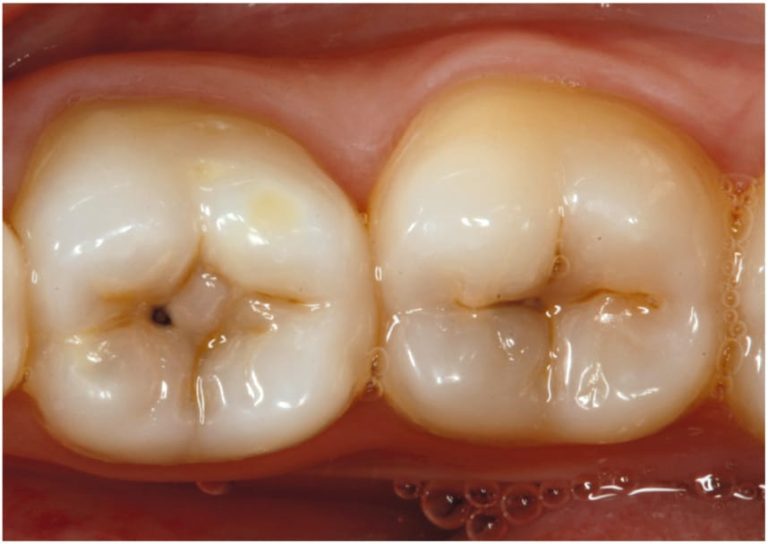

De acordo com o especialista, a cárie sempre começa de forma discreta, mas tende a evoluir com o passar do tempo quando não é tratada.

“O risco maior é a perda do dente. A cárie começa pequena e, conforme você não resolve o problema, ela vai aumentando”, explica.

Com o avanço da lesão, as consequências vão além do desconforto inicial. “O paciente pode ter dor, inflamação e, se essa cárie atingir partes mais profundas do dente, como o nervo, isso acaba causando dor intensa”, afirma Grandal. Ele compara o processo à ferrugem: “É como uma ferrugem na base de uma geladeira. Se não for removida logo, ela vai crescer cada vez mais”.